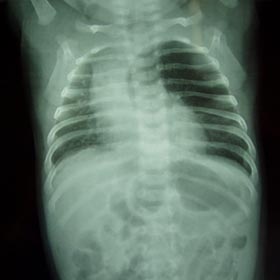

Intestinal Atresias

Atresia may occur at any level. Number & distribution of dilated bowel loops will, therefore, vary & an idea about the site of obstruction can be inferred from it. Over the years, I have mastered the art of anastomosis in newborn patients.